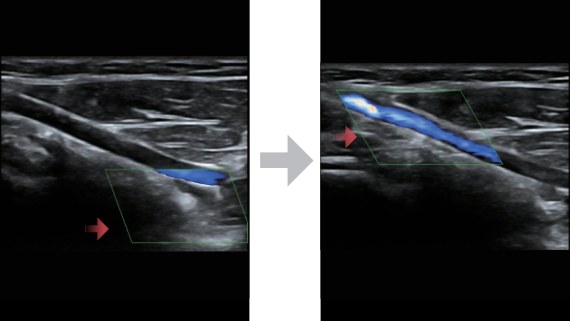

X-Insight is een inzichtelijke oplossing om meer visie te krijgen.

De gloednieuwe oplossing van Mindray is het geslaagde product dat is voortgekomen uit voortdurende klantinzichten in klinische behoeften in combinatie met steeds evoluerende, geavanceerde ultrasoundtechnologie?n. Vol energie en gebrand op toekomstgerichte inzichten en eindeloze mogelijkheden: dankzij de verhoogde schaalbaarheid wordt de oplossing continu verbeterd.

De DC-60 Exp met X-Insight is ontworpen op basis van diepgaand inzicht in klantbehoeften om hoge effici?ntie met nauwkeurige beeldverwerking te leveren, dankzij eXacte helderheid, eXceptionele intelligentie en eXcellente ervaring.